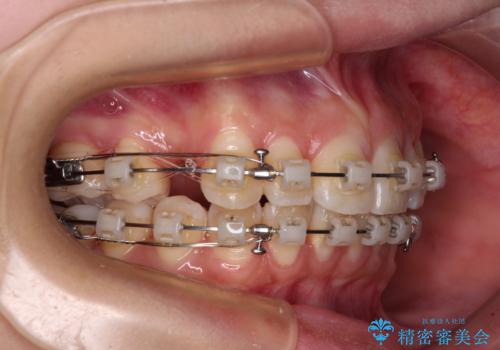

- 矯正装置

- クリアブラケット

- 治療計画

- 口を閉じたときに唇の間から飛び出してくる前歯を気にして来院された患者様です。

骨格的に上顎骨が前方位にあるため、左右の第一小臼歯を抜歯し、ワイヤー装置にて咬み合わせを整えていくこととしました。